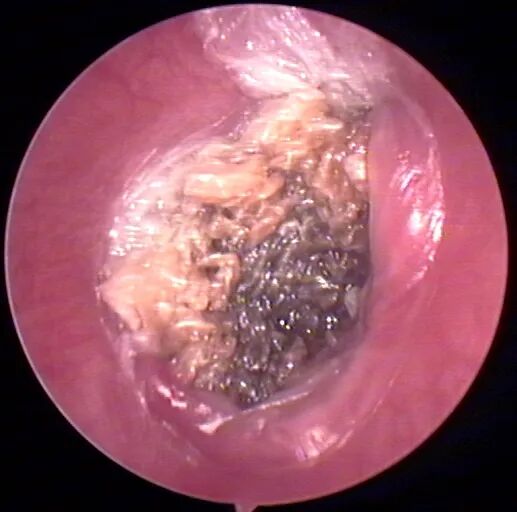

像这样的:

但是有时虽然看不到菌毛和孢子,但实际上也是真菌感染,比如: